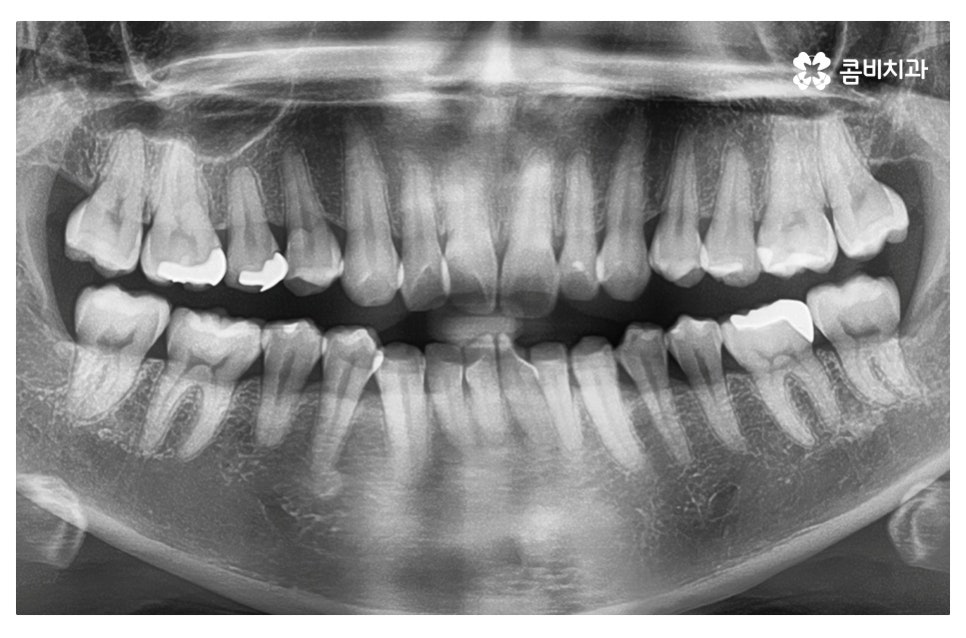

이번 포스팅에서 보인 덧니교정 사례의 경우 기능이 적은 작은 어금니를

발치하여 교정이 진행되었으며 발치를 진행하는 경우

작은 어금니를 발치하는데 충치 등으로 인해 손상이 큰 치아를

발치하는 경우가 일반적이라고 할 수 있어요.